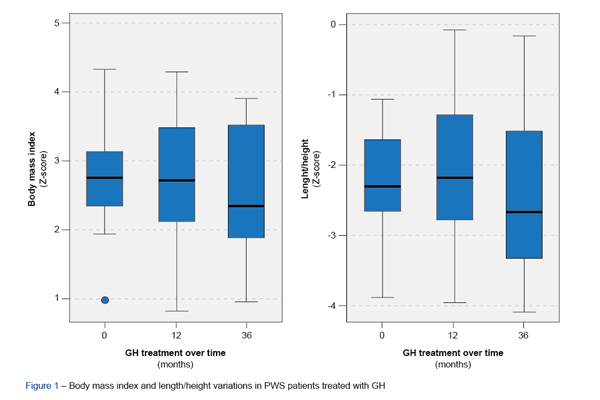

Introdução: A síndrome de Prader-Willi é uma doença genética multissistémica associada a baixa estatu...